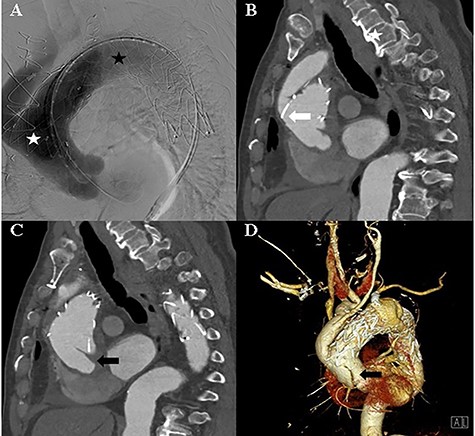

An 82-year-old man with a history of atypical chest pain was diagnosed with an aortic aneurysm with an eccentric mural thrombus at the distal arch. The thrombus had a maximum diameter of 70 mm starting directly below the ostia of the common carotid artery (Fig. 1). There were no abnormal findings, except for mild aortic regurgitation on preoperative echocardiography. We planned to perform a hybrid thoracic endovascular aortic repair and decided to carry out the debranching operation first. A type I hybrid arch debranching operation was performed; an 18-mm Gore-Tex graft was used from the ascending aorta to the innominate artery, and another 8-mm Gore-Tex graft was used from the innominate artery to the left common carotid artery in Spielvogel fashion (Fig. 1). There were no post-operative complications.

A and B: Computed tomography of the chest shows an aortic aneurysm (white asterisk) with a mural thrombus (black asterisk) at the distal arch. C and D: Post-debranching operative computed tomography of the chest shows the graft, which is directly sutured onto the ascending aorta (black arrow), and the graft used from the innominate artery to the left common carotid artery (white arrow).